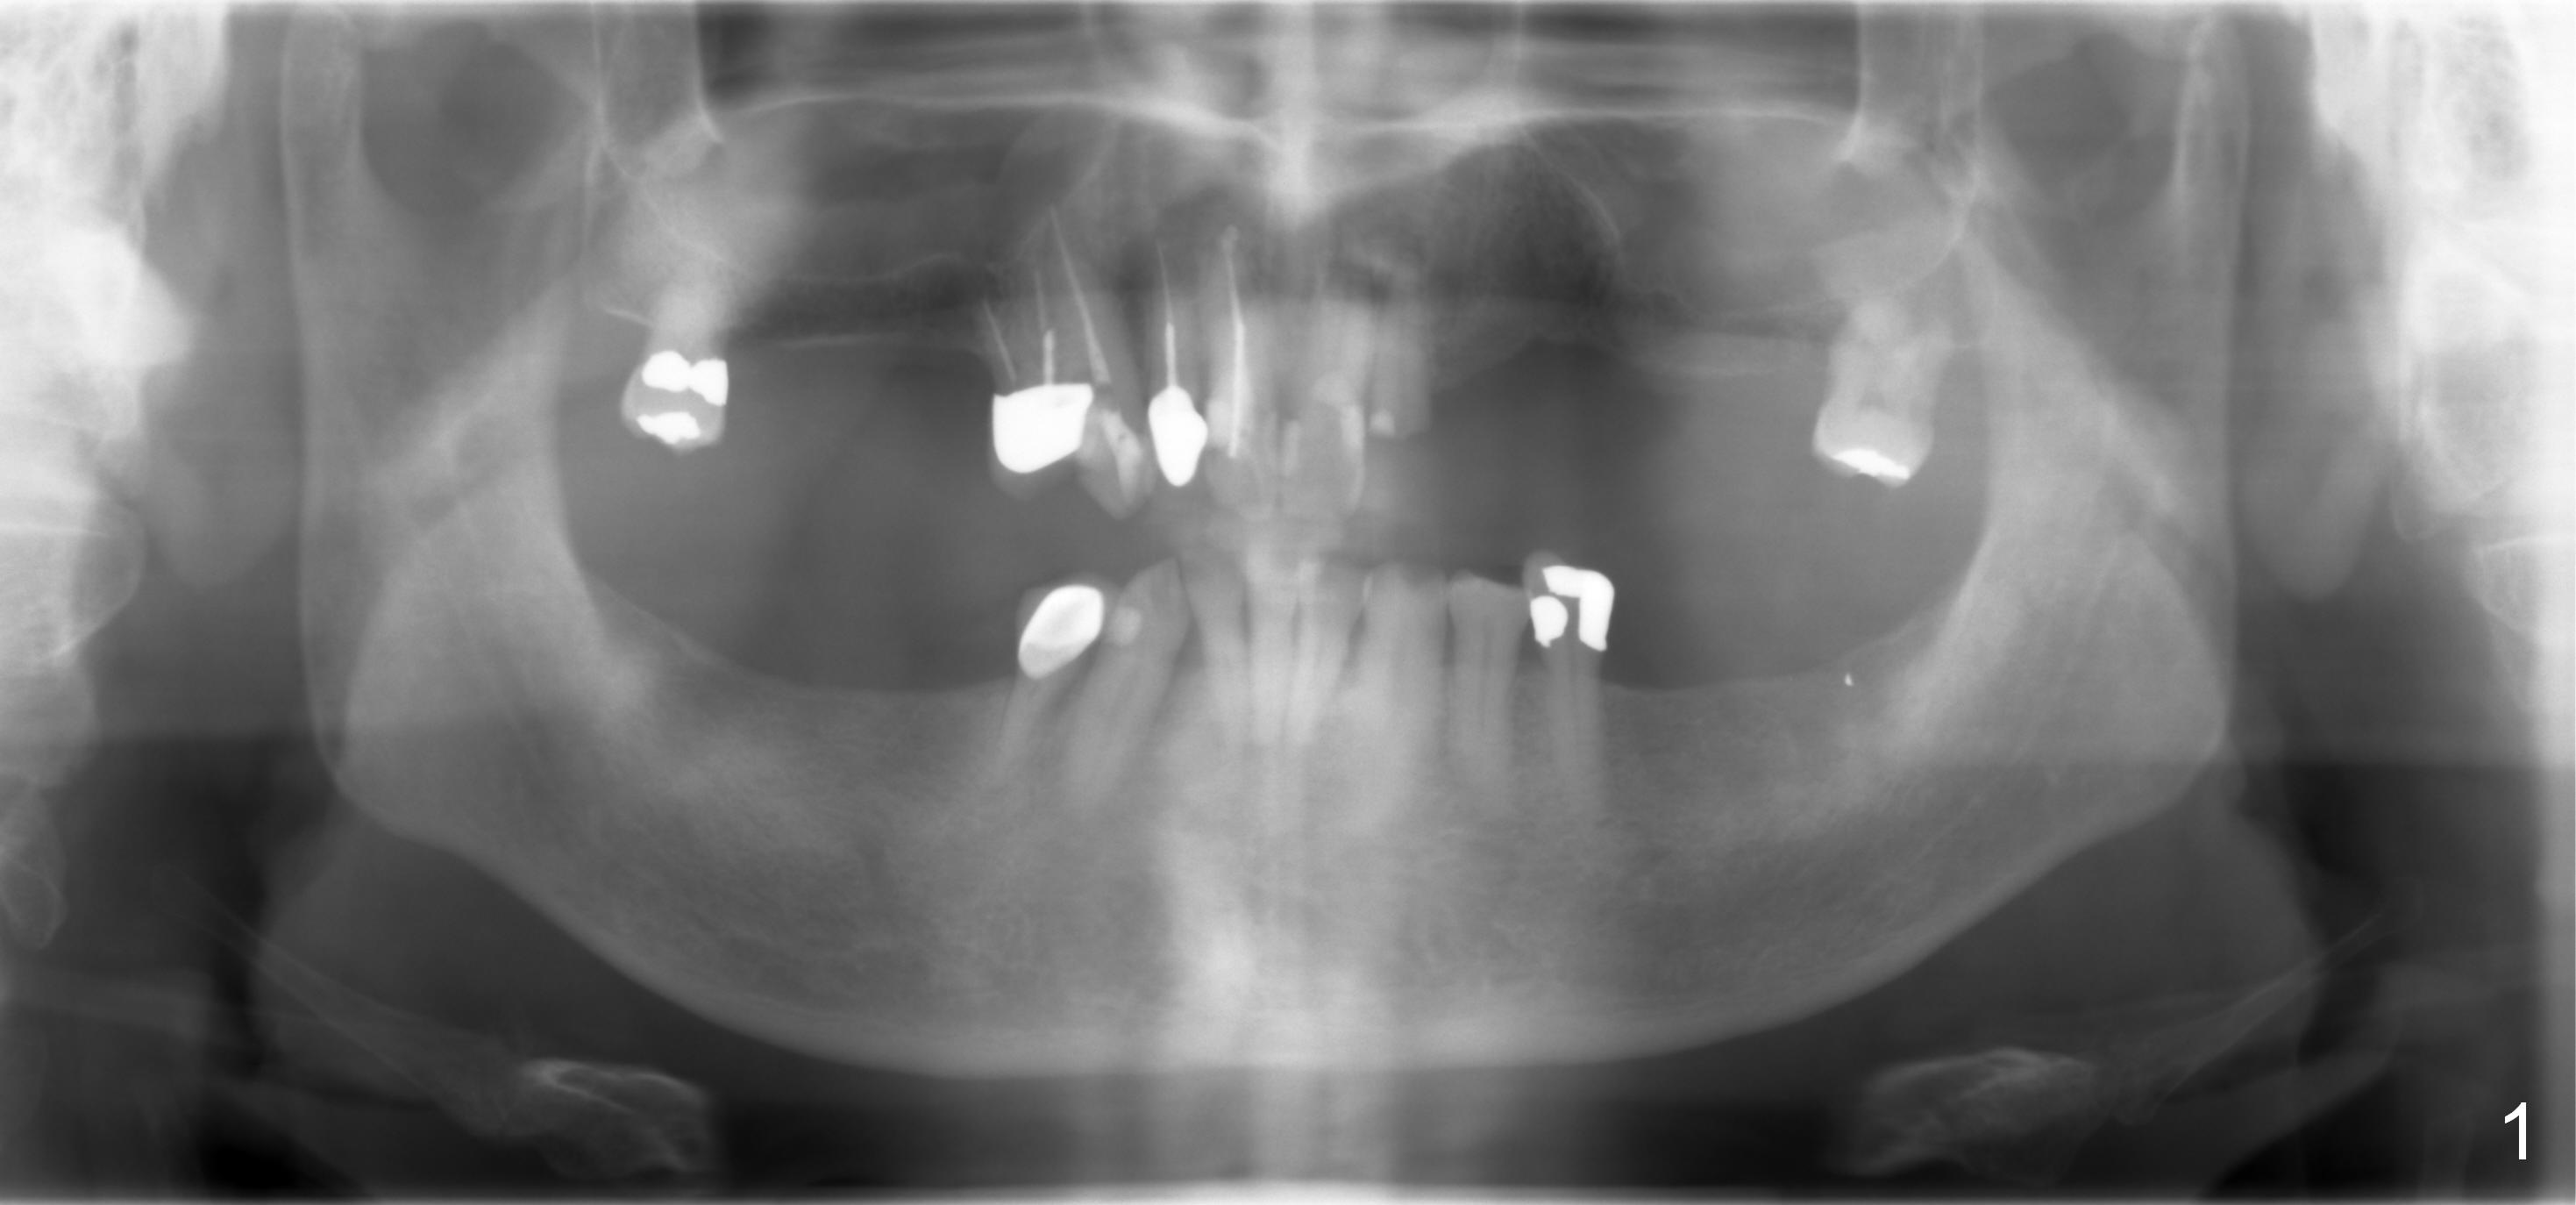

A 70-year-old man (TF) requests implant restoration for the upper left quadrant first (Fig.1), exactly #10 and 11 first (Fig.2-4). There is periapical radiolucency associated with the residual root at #10 (Fig.2 *). Local antibiotic will be Metronidazole. The root of #10 is long and large. The bone at #11 looks loose. Long implants will be placed (Fig.4). Osteotomy preparation should be less.

When initial osteotomy is established at #10 with insertion of a parallel pin, use 4.5 mm implant spacer to determine the initial point for #11 implant site (Fig.4: 6.49 (red line)-2=4.49 mm). 70岁男多个牙齿缺失,5.5年前就诊,同意在10-13位点植牙(图一)。